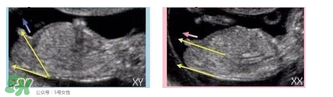

主要通過(guò)尾椎那里判斷。 為了讓大家更直觀一些,我找兩個(gè)比較明顯的圖,男左女右,大家看男孩兒的特征點(diǎn)與身體呈45度角,還多一些,而女孩兒的特征點(diǎn)幾乎和軀體平行。圖第一張男寶,第二張女寶

用線條表示一下就更直觀了.當(dāng)然,這也不是完全絕對(duì)的,如果你們發(fā)現(xiàn)自己的寶貝兒與心想的不一樣,那這理論不一定對(duì),不是絕對(duì)的.千萬(wàn)不要因?yàn)檫@個(gè)而影響自己孕期心情,寶寶健康是第一位的,我只是把自己所了解到的知識(shí)給大家普及一下。